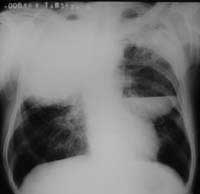

以下是引用woaixct在2006-6-23 12:15:00的发言:[br]第一张胸片示:右肺上叶为大片致密影占据,左肺上见大片致影及空洞性病灶并有液平;[br]第二张胸片示:左肺上叶致密影及空洞性病灶基本吸收,而右肺上叶之病灶有少许吸收改变;[br]ct片示:右上叶大片软组织密度,右肺门区至右肺上叶见巨大软组织块,内见支气管充气征,上纵隔右移,主气管及上叶支气受压变扁,中间支气管狭窄,左肺上叶空洞性病灶并有液平,左肺上叶尖后段见大片致密影,结合2张胸片考虑,ct片是4月份所摄,而不是6月份的片子;[br]结合2张胸片及ct片考虑:[br] 1.右中央型肺癌伴右肺上叶不张;[br] 2.左肺上叶尖后段炎性变及左肺脓肿;[br]第2张胸片提示:经过一个多月的不规则抗炎治疗,左肺上叶病灶及右肺上叶不张病灶基本吸收,而右肺占位无明显变化。